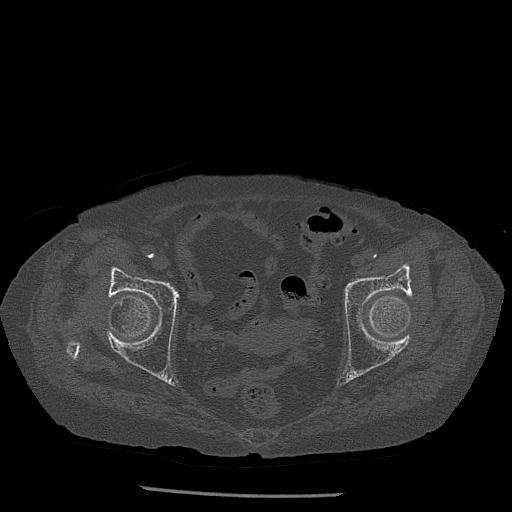

100703 1/27 両股正面+軸 1/29 両股正面+軸 94歳女性 パンソンロン